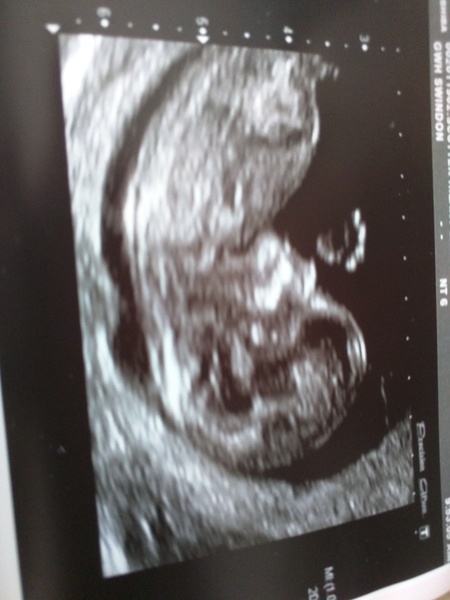

good morning ladies, had my scan today midwife dates me at 11+6 so according to my app I'm back to having a Brussels sprout in there (until tomorrow!) will have to go on the web app to upload a picture of bean. apparently bean was being very stubborn and was fast asleep curled up and we had to do a bit of waking up to get a proper measurement to which baby threw a strop and wriggled about a lot!! new due date is now 6/10/15! Smile Smile Smile Smile

MrsEvansAlmost · 23/03/2015 12:19

Here is Baby Evans waving hello to all on mums net!

X post Mrs e! Amazing pic, hello baby!!

Congrats to everyone getting scans - MrsE your pic is lovely!